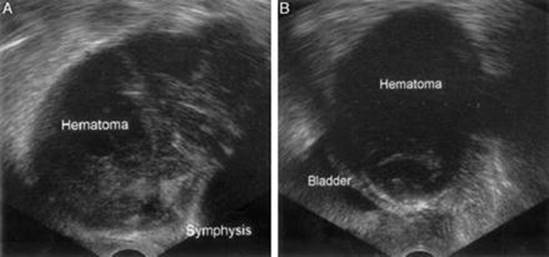

If a patient has pain and swelling consistent with retropubic hematoma, obtain a complete blood count and coagulation studies. In patients who are hemodynamically stable but with ongoing pain and distention, an ultrasound may be obtained to visualize a retropubic hematoma, either transabdominally or transvaginally (Fig. 19.2). Alternatively, a CT scan of the pelvic with IV contrast can be obtained (Fig. 19.3); extravasation of contrast may be identified in the retropubic space.

Fig. 19.2

Retropubic hematoma by transvaginal ultrasound, following a tension-free vaginal tape procedure. (a) Sagittal view. (b) Horizontal view. A nonhomogeneous mass behind the symphysis representing a clotted hematoma is displacing the bladder to the right (Flock et al. [22], with permission of the American College of Obstetricians and Gynecologists)